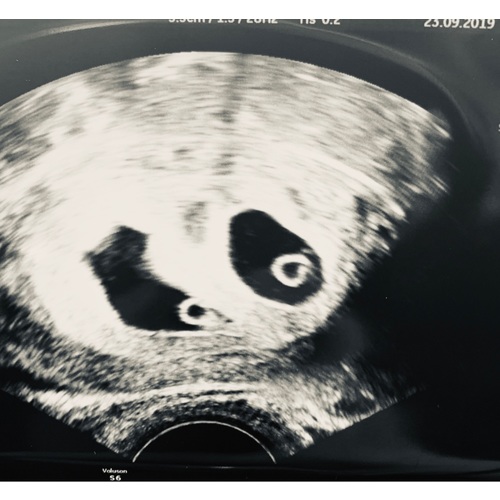

Dit is mijn echo van gisteren 5+5. Ook 2 vruchtzakjes en bij beide een hart ...

Ik ging naar de verloskundige met hele erge buikkrampen. Kreeg voor de zekerheid een echo omdat het me niet lekker zat en we volgende week op vakangie gaan naar het buitenland. Tijdens de echo zag ze eerst 3 holtes.. Toen schrok vooral mijn man heel erg.. toen ze daarna zei, het zijn er 2.. viel het voor ons dus alweer mee! Het is onze eerste zwangerschap, dus allemaal super spannend en nieuw. Verloskundige dacht dat ik ongeveer 5 +5 zwanger ben en dat het daarom nog even afwachten is hoe het zich verder ontwikkeld omdat dit wel een hele vroege echo was. Wel beide hartjes zien kloppen.. durf er nog niet van uit te gaan dat het allemaal goed gaat, omdat ze zelf ook eerst de volgende echo wilde afwachten. Vind het dus vooral spannend of het over anderhalve week nog steeds allemaal goed is. Hoe was het bij jou?